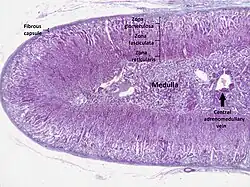

Section of human adrenal gland under the microscope, showing its different layers. From the surface to the center: zona glomerulosa, zona fasciculata, zona reticularis, medulla. In the medulla, the central adrenomedullary vein is visible.

The adrenal cortex is the outer region and also the largest part of an adrenal gland. It has three layers, or zones: zona glomerulosa, zona fasciculata and zona reticularis. Each zone is responsible for producing specific hormones. When viewed under a microscope, each layer has a distinct appearance and each has a different function.[13] The adrenal cortex produces hormones, namely aldosterone, cortisol and androgens.[14]